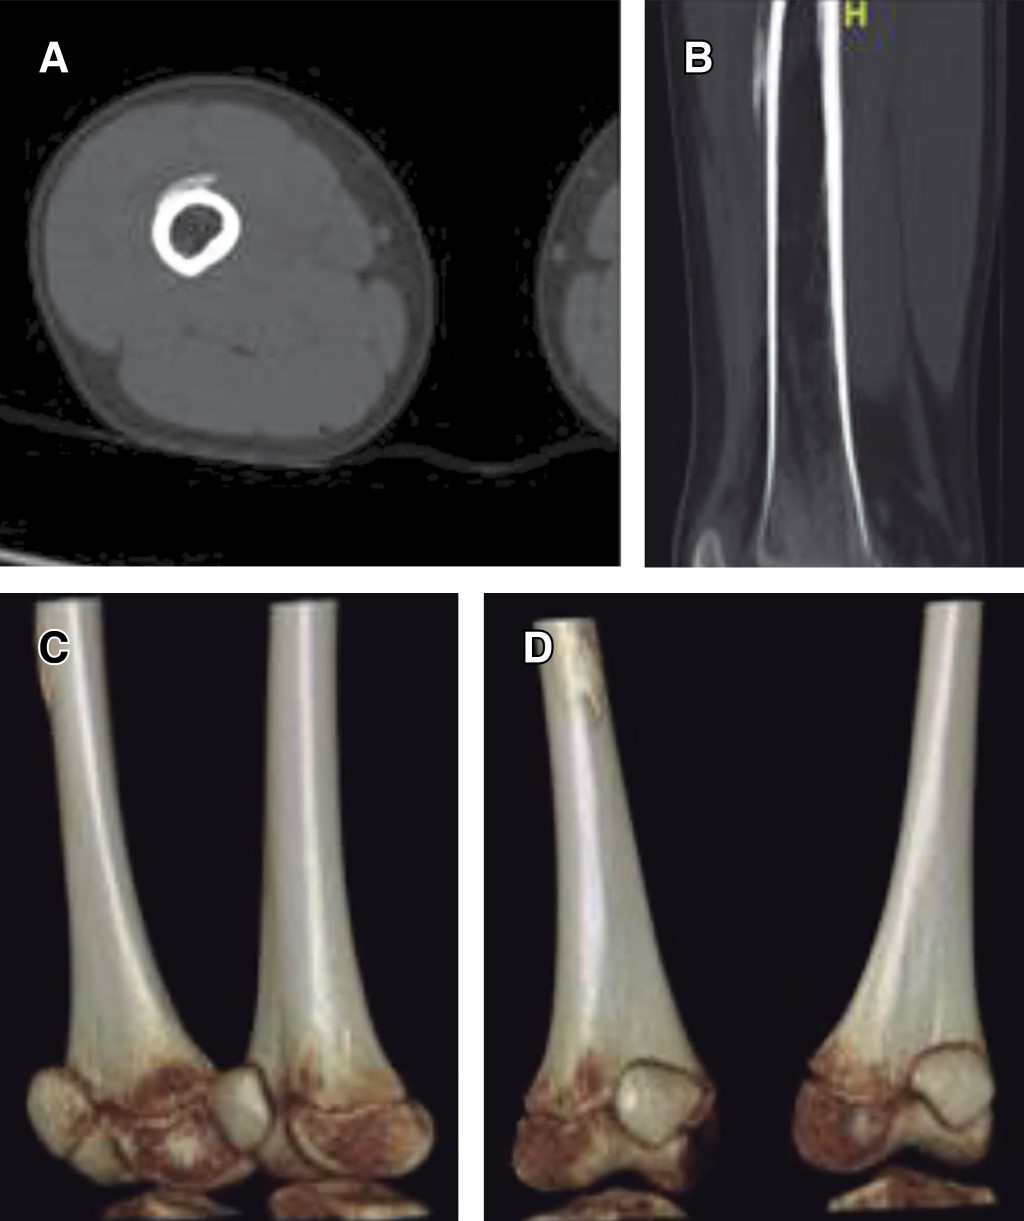

Introduction: myositis ossificans (MO) is described as a non-neoplasic heterotopic bone formation at soft tissues and muscle. It is a rare entity in children, but it must be included within the differential diagnosis of a malignant tumor or an infection. Material and methods: the objective of this retrospective study is to describe three clinical cases of circumscribed myositis ossificans; the first one is a 10-year-old girl with a post-traumatic cervical injury, the second one is an 11-year-old boy with an atraumatic-type distal thigh injury, and the third one is an 8-year-old boy with a post-traumatic right thigh tumor. Results: the diagnosis was made on the basis of the clinical presentation, radiologic imaging and histopathological findings. The results obtained by conservative treatment were good in all cases, with resolution of pain and progressive reduction in size of lesions, without registering complications during follow-up. Conclusion: myositis ossificans is a rare entity, whose diagnosis is usually complex and may require a multidisciplinary team, and whose prognosis is nevertheless favorable.

Figure 1

Figure 2

Figure 3

Figure 4

Figure 5

Figure 6